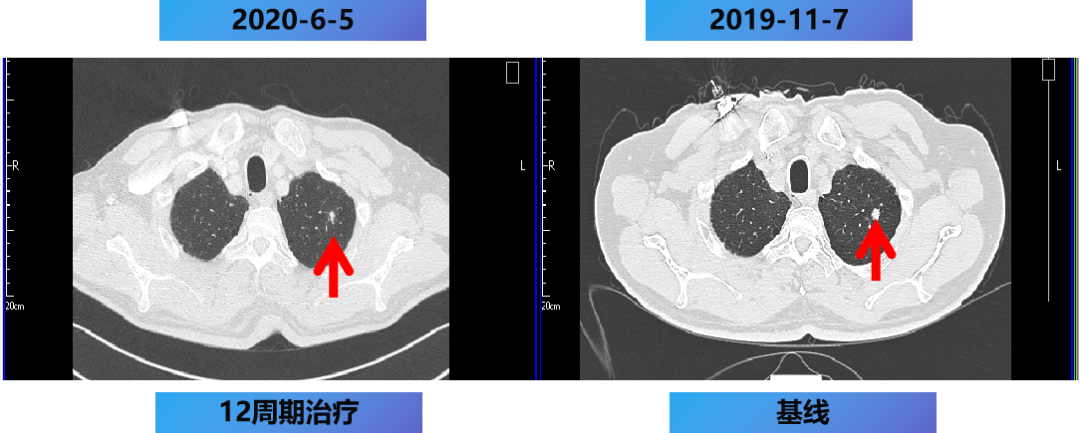

1. 乙状结肠部位高代谢病变,肝内多发高代谢灶,左肺上叶尖后段高代谢结节,以上均考虑恶性,乙状结肠癌伴左肺及肝脏转移可能性大。

【治疗方案疗效评估】

MDT意见:肝转移灶可切除,肺转移灶缩小。

治疗目标:NED。

治疗策略:原发灶切除和肝转移灶切除,肺转移灶择期手术。

12周期化疗+手术+肝转移灶切除及消融。

2020-7-5 复查腹部MRI示:乙状结肠癌伴肝转移治疗后改变,对比2020-6-18 MRI,肝内治疗灶凝固坏死显著,肝内未见明显癌灶征象,部分周边反应性改变可能,建议3个月后随诊复查。